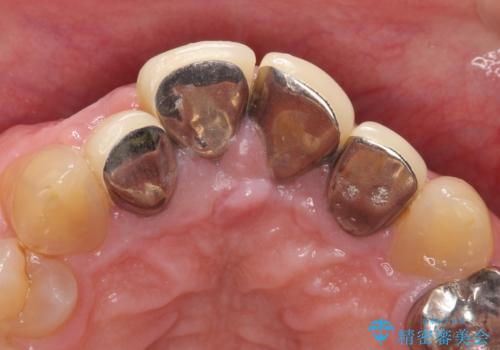

- 前歯の見た目が気になるといらっしゃった方の症例です。

再根管治療後、オールセラミッククラウンによる補綴を行いました。

右上2は歯茎のラインを整えるため歯周外科を行っております。

- オールセラミッククラウン…¥100,000×4、仮歯…¥10,000×4、ファイバーコア…¥20,000×4、歯周外科…¥100,000、精密根管治療費別途費用は治療当時の料金となります